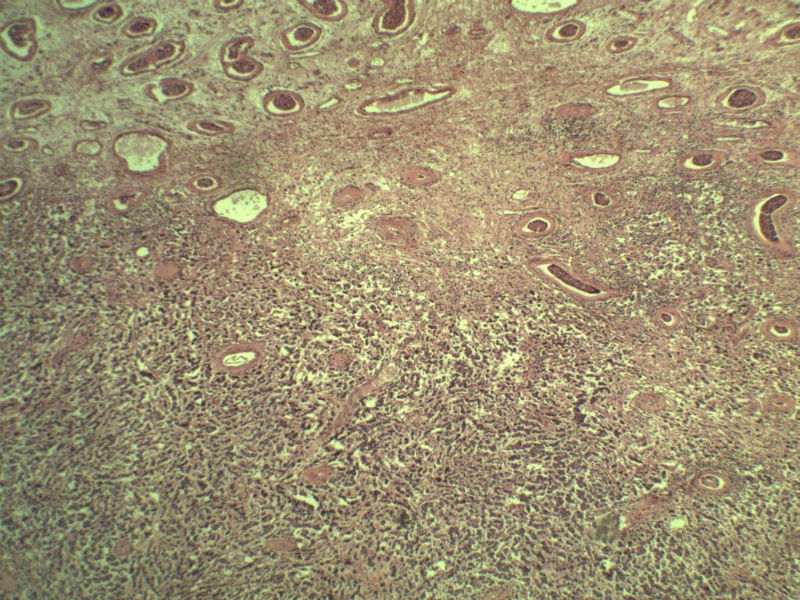

男 27岁 腹腔隐睾 5*3*2 cm, 切面灰红灰黄、实性、质中,请各位老师看看,是精原细胞瘤吗?感觉不像.腹腔隐睾图1

典型的精原细胞瘤,隐睾易恶变